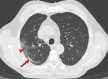

Chest CT has a potential role in the diagnosis, detection of complications, and prognostication of coronavirus disease 2019 (COVID-19). Implementation of appropriate precautionary safety measures, chest CT protocol optimization, and a standardized reporting system based on the pulmonary findings in this disease will enhance the clinical utility of chest CT. However, chest CT examinations may lead to both false-negative and false-positive results. Furthermore, the added value of chest CT in diagnostic decision making is dependent on several dynamic variables, most notably available resources (real-time reverse transcription-polymerase chain reaction [RT-PCR] tests, personal protective equipment, CT scanners, hospital and radiology personnel availability, and isolation room capacity) and the prevalence of both COVID-19 and other diseases with overlapping manifestations at chest CT. Chest CT is valuable to detect both alternative diagnoses and complications of COVID-19 (acute respiratory distress syndrome, pulmonary embolism, and heart failure), while its role for prognostication requires further investigation. The authors describe imaging and managing care of patients with COVID-19, with topics including (a) chest CT protocol, (b) chest CT findings of COVID-19 and its complications, (c) the diagnostic accuracy of chest CT and its role in diagnostic decision making and prognostication, and (d) reporting and communicating chest CT findings. The authors also review other specific topics, including the pathophysiology and clinical manifestations of COVID-19, the World Health Organization case definition, the value of performing RT-PCR tests, and the radiology department and personnel impact related to performing chest CT in COVID-19. ©RSNA, 2020.